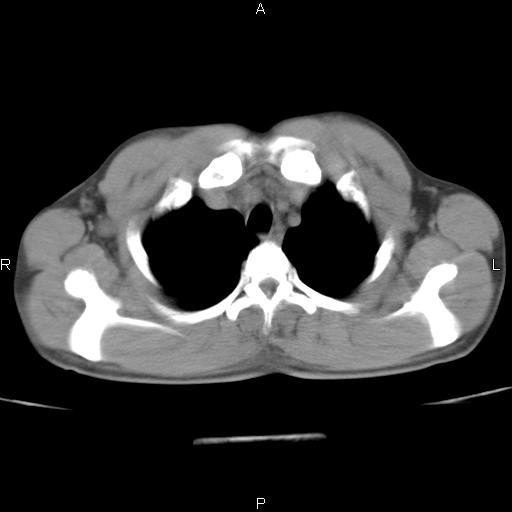

患者,男,40岁。间断发热,咳嗽二十余日。体温最高达38.9° 在当地诊所抗炎治疗三天后体温降至正常,患者自行停药。今又发热。胸片示,左下肺阴影。

左下肺片状高密度影,境界模糊,密度不均,考虑感染性病变可能性大,建议抗炎治疗后复查。左肺门增大,不除外占位性病变,必要时支气管镜检。